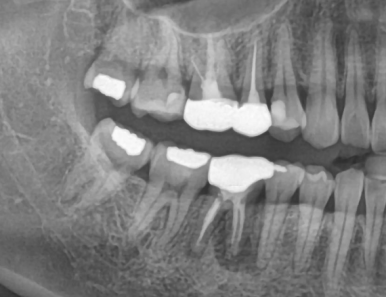

4. 신경치료 후 통증이 반복되거나 재감염되는 경우

신경치료를 두세 번 받았음에도

통증이 계속 반복되거나 염증이 재발된다면

치아 기능이 이미 한계에 도달한 상태일 수 있습니다.

| 발치 전 | 발치 후 염증제거, 임플란트 식립 |

이런 경우엔 더 큰 손상을 막기 위해

적절한 시점에 발치 후 임플란트를 계획하는 것이 안전합니다.